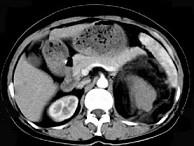

问题 女,64岁,左侧腰部胀痛,行CT扫描,下列说法正确的是()

选项 A.左肾区可见一巨大的占位性病灶,境界较清楚,胰腺尾部受压向前推移 B.该病灶密度不均匀,其内可见脂肪密度影,且呈不均匀强化 C.考虑为左肾来源的血管平滑肌脂肪瘤 D.考虑为左侧肾上腺来源的髓样脂肪瘤 E.考虑为腹膜后来源的脂肪肉瘤

答案 ABC